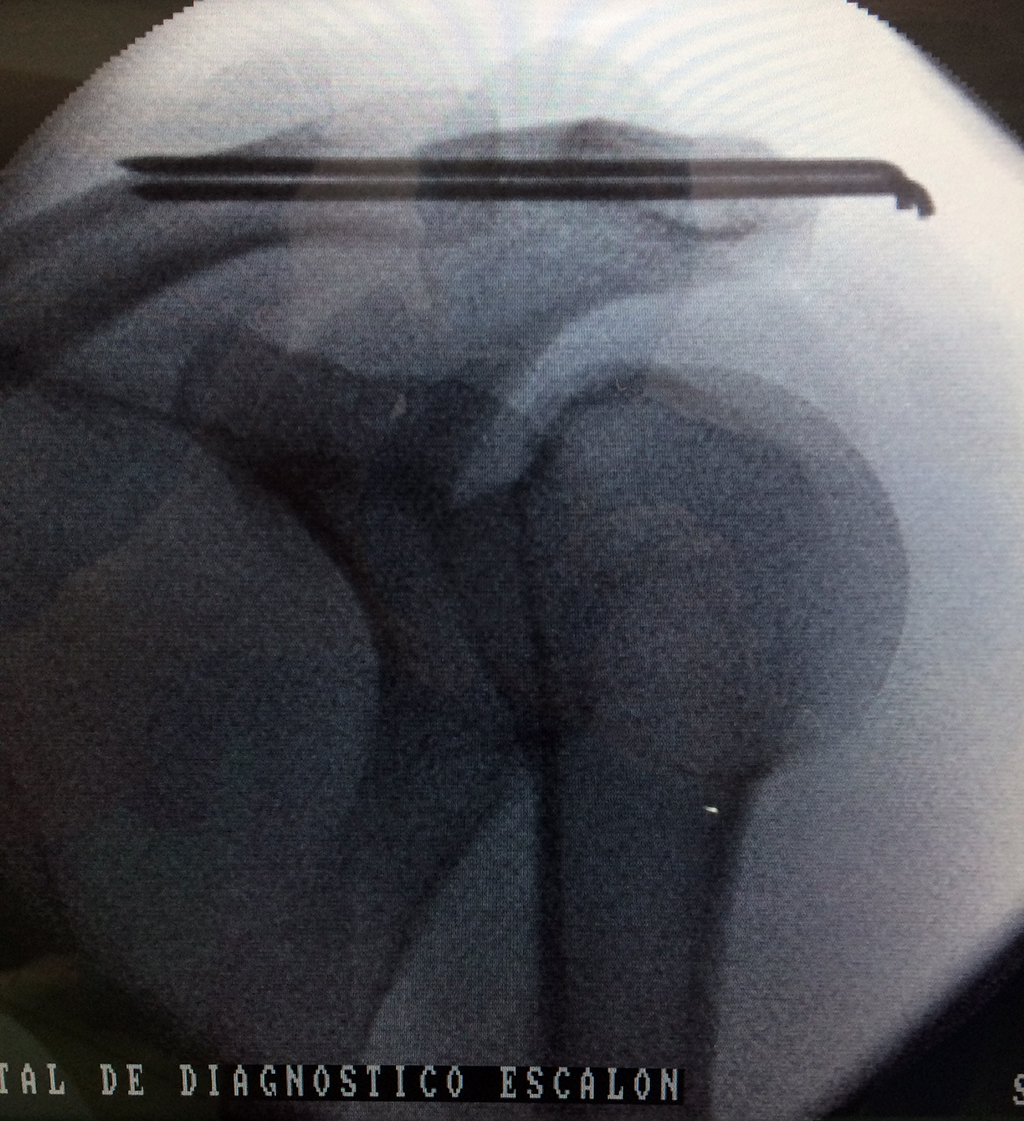

Cirugias en El Salvador - Clavícula